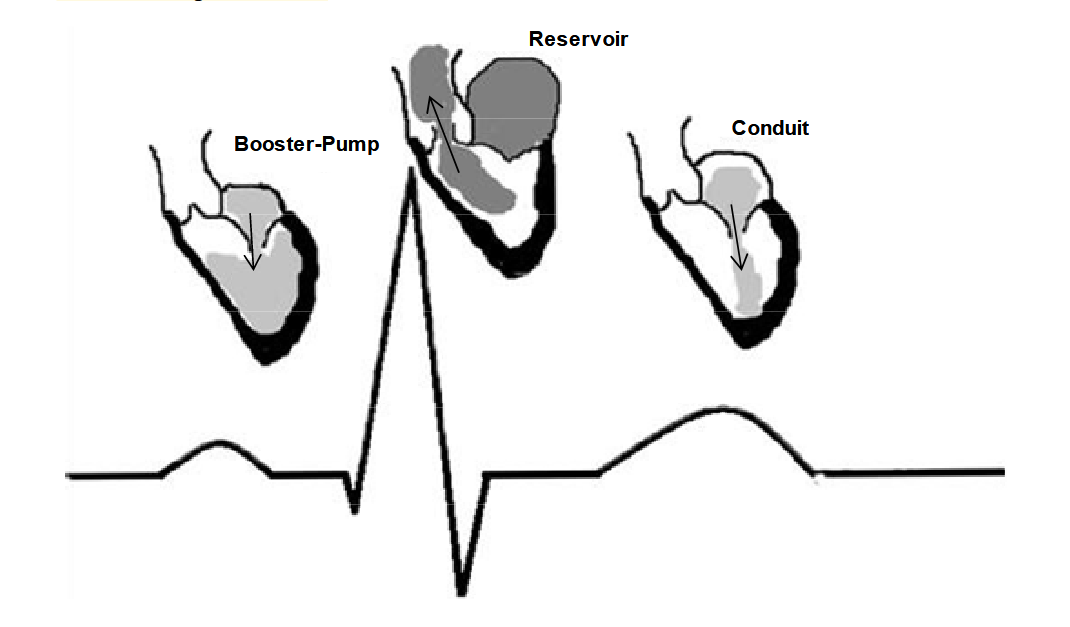

Left atrial function has been typically divided into three integrated phases: reservoir, conduit and booster-pump (Figure 1) [7–10]. Reservoir: an expansion phase during left ventricular (LV) systole; the LA stores pulmonary venous return during LV contraction and isovolumic relaxation. Conduit: the LA transfers blood passively into the LV during ventricular diastole. Booster-pump: contractile component (when supraventricular rhythm is present);